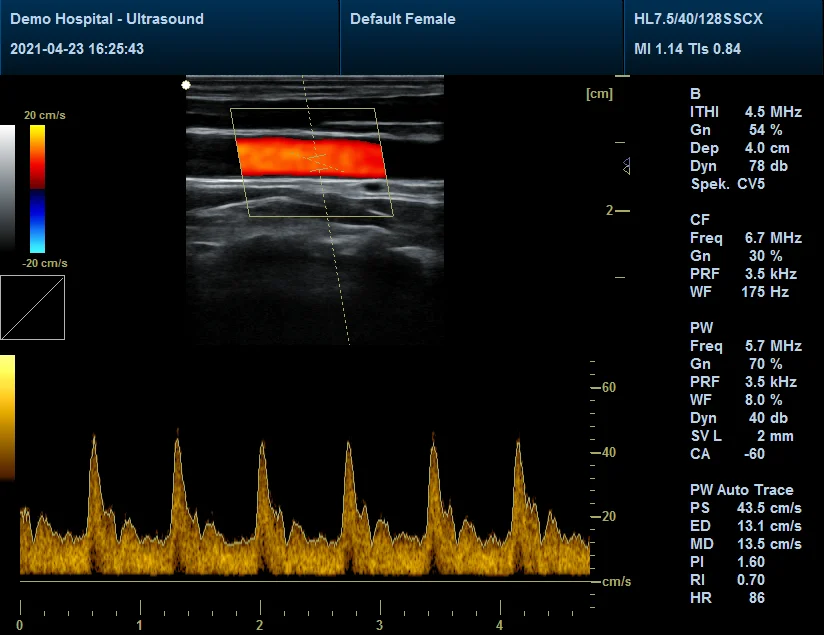

B+PW (Real Duplex),B+CF/PDI/DPDI+PW (Real Triplex)

PRF repetition frequency range:0.6-20 kHz

Real-time tracking spectrum and real-time calculation of spectrum parameters

distance, depth, area, circumference, volume, angle, stenosis ratio, ratio, speed, gradient (PG), acceleration, resistance index (RI), heart rate, velocity time integral (VTI), etc.

Scanning Images